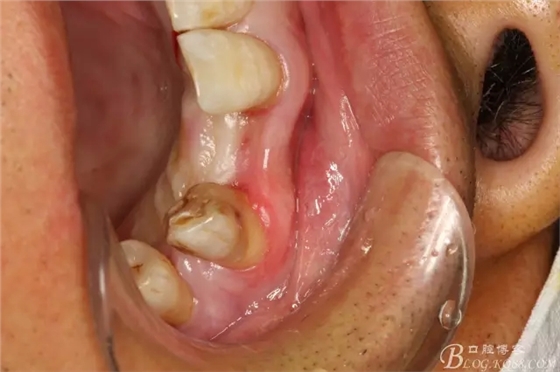

圖5.腭側(cè)觀:牙槽嵴豐滿度尚可。